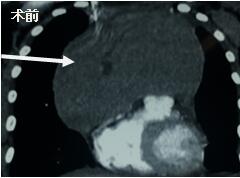

當看到病人的CT等外院各項檢查時,我頭皮發(fā)麻,心頭發(fā)怵:巨大的腫塊占據(jù)著整個縱隔,壓迫心臟,與血管關(guān)系密切,初步考慮侵襲性胸腺瘤、胸腺癌或淋巴瘤等,合并腎功能不全,無法完整切除,手術(shù)風險大,手術(shù)并不能提高病人長期生存率,換言之,小伙子等待的是生命的立即終結(jié)。